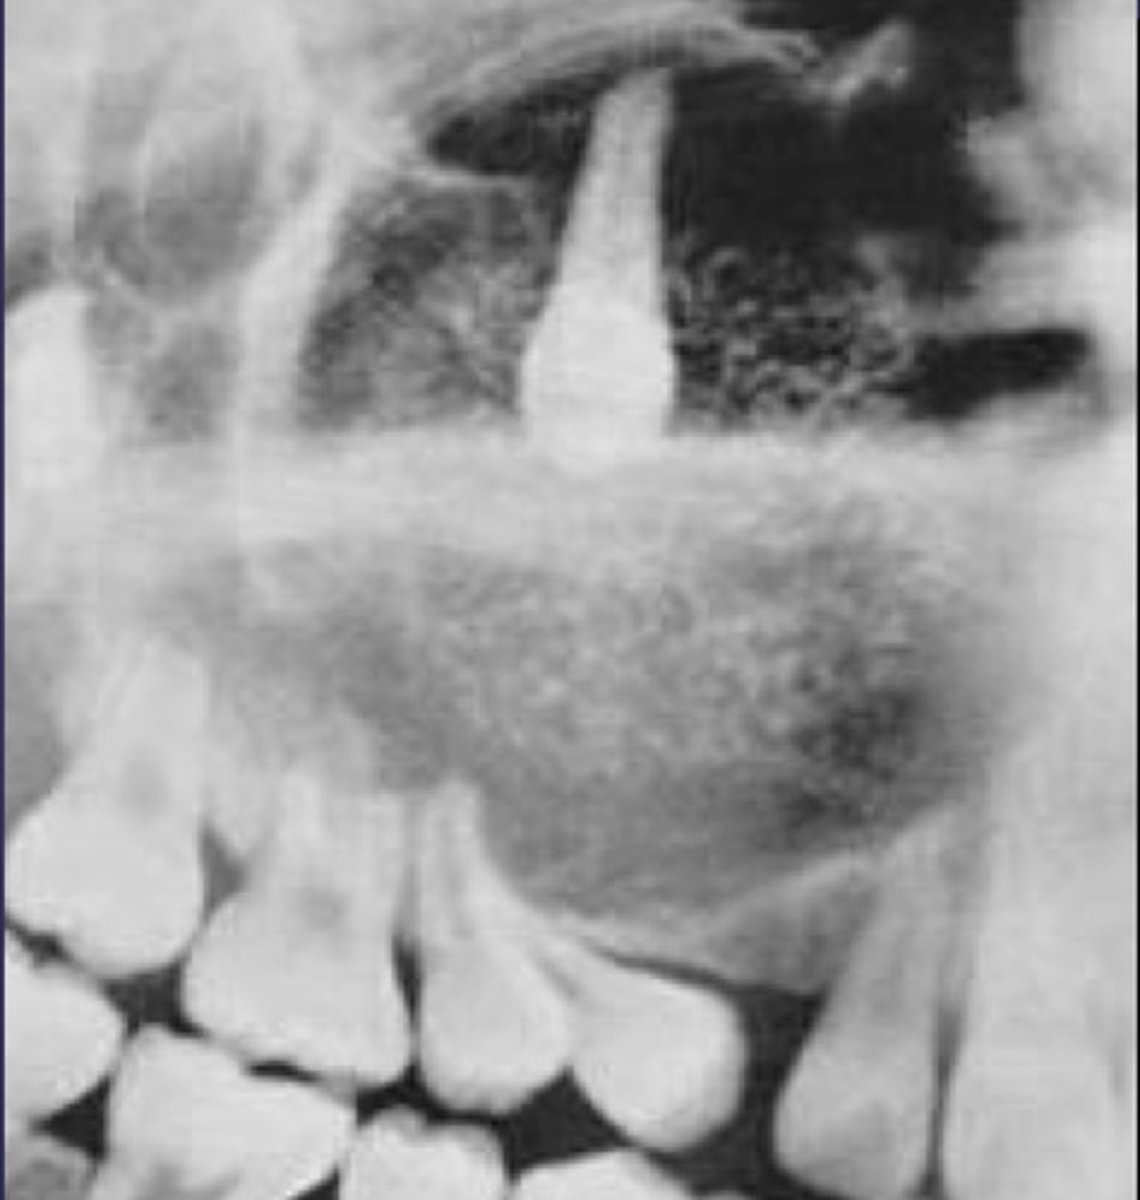

A. well-defined, corticated, pericoronal radiolucency associated with tooth number 7

B. well-defined, non coritcated periapical lesion associated with tooth number 6

C. ill-defined, corticated periapical lesion associated with tooth number 6

D. ill-defined, corticated periapical lesion associated with tooth number 5

(root resorption also seen)

What category would you put this lesion into?

Benign odontogenic tumor/cyst

What would be a differential diagnosis for this lesion?

- AOT

- Calcifying Epithelial Odontogenic Tumor (Pindborg tumor)

- Calcifying Epithelial Odontogenic Cyst( Gorlins cyst)